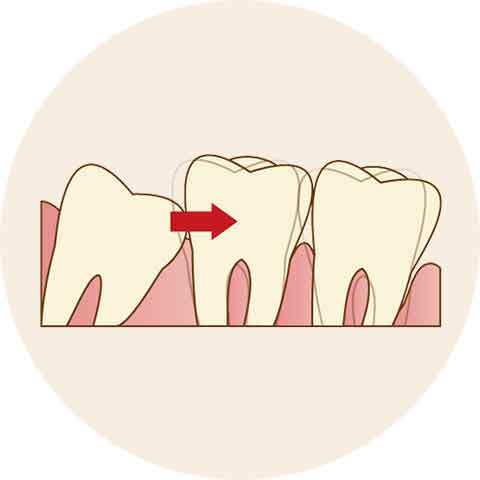

歯並びを乱す原因になっている場合

特に、親知らずが斜めや横向きに埋まっている場合、手前の歯を押して歯並びが乱れてしまう原因になることがあるため、放置はおすすめしません。